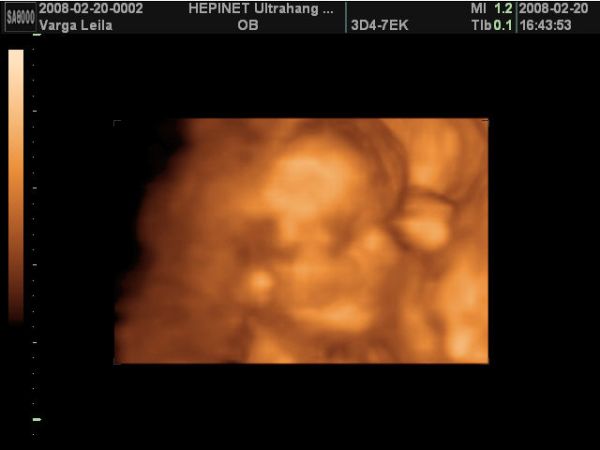

A babó a vizsgálat alatt végig tornázott, izgett-mozgott, úgy nevettem közben, mert annyira jó volt látni, hogy ficánkol, meg homorít a hátával.

A lába között volt a köldökzsinór, és hát eléggé ficánkolt is, úgyhogy csak egyszer láttunk valamit, mikor terpesztett 2D-ben. A nő azt mondta, hogy olyan fiúsnak látszik, de még nem mer biztosat mondani. Szerintem is az lesz, mert én is úgy érzem. De azért a 18. hetin már remélem jól fog látszani.

Aztán a legvégén nagyon befúrta magát a méhfalba, úgyhogy az arcát nem tudtuk jobban megnézni.